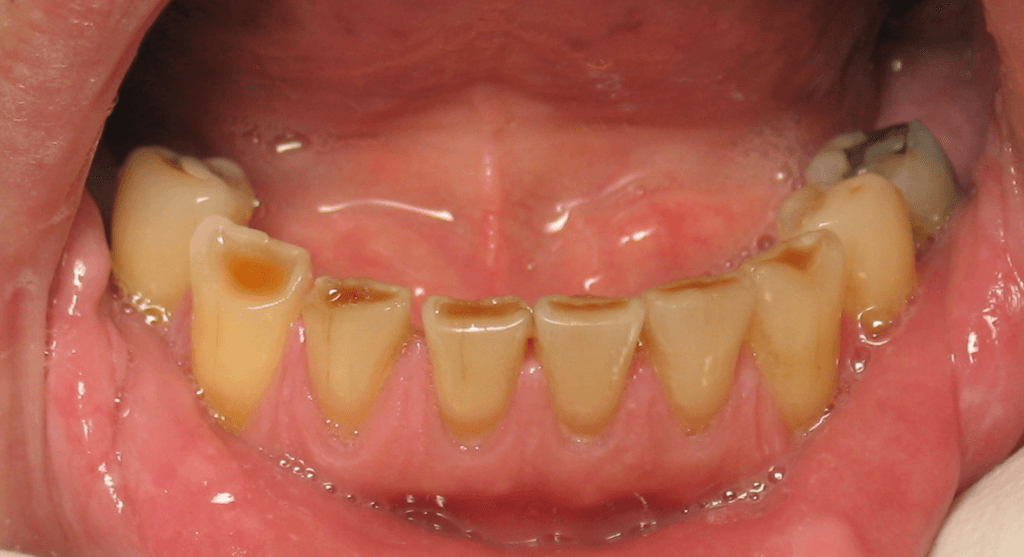

Bruxism is the habit of clenching or grinding your teeth. Your teeth are not meant to stay tightly together or in constant contact. Normally, your upper and lower teeth should only touch briefly when you swallow or chew.If your teeth are in frequent contact or you grind them continuously, this can wear down the tooth enamel—the hard outer layer that covers each tooth. Without enamel to protect the inner structures of your teeth, you may develop various dental problems.Regular clenching or grinding can also cause pain in the jaw joint or in the facial muscles. Bruxism most often occurs during sleep, but some people also experience it while they are awake.